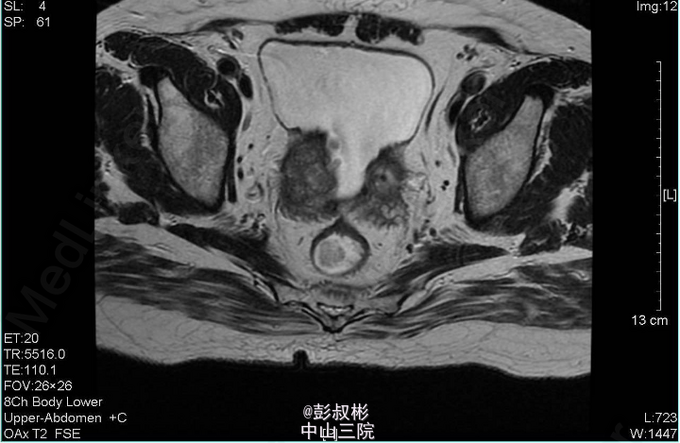

4、查体:直肠指检:前列腺明显增大,大小约:7×6cm,质韧,中央沟消失,可触及一3*2cm结节,质硬,无压痛,界清,指套未见染血 5、辅助检查:外院查尿常规示:红细胞31022个/ul,CA19-9:60.9U/ml,F-PSA:6.45ng/ml,T-PSA:21.2ng/ml,彩超示:膀胱区及前列腺内低回声团,盆腔CT示:膀胱癌并前列腺转移。我院血常规:血红蛋白浓度119.000g/L,白细胞总数7.340x10E9/L。 尿常规:潜血+++,红细胞计数12050.20个/ul,白细胞计数49.50个/ul。 生化全套:肌酐(酶法)218.800umol/L,尿酸658umol/L,血淀粉酶227U/L,谷丙转氨酶64 U/L,谷草转氨酶49U/L,谷氨酰转肽酶340U/L。 PSA两项:总前列腺特异性抗原22.362ng/ml,游离前列腺特异性抗原5.957ng/ml。 盆腔MR:1、考虑前列腺癌并出血,膀胱后壁、双侧精囊腺受压。2、右侧耻骨联合小结节,考虑转移瘤可能性大;左侧坐骨结节所见,未除外转移瘤可能。3、考虑右侧股骨头坏死。胸片示:主动脉硬化,心电图正常。 肺功能:通气功能大至正常。 心脏彩超:EF 65%。主动脉瓣钙化并反流(轻度)。左室收缩功能正常。左室舒张功能减退。 动态心电图:1、窦性心率。2、稀发房早。3、肢体导联低电压 肝胆胰脾彩超:胰头稍大,慢性胆囊炎声像,胆囊多发结石,轻度脂肪肝。 前列腺穿刺:结果未出 骨扫描:全身未见骨转移瘤